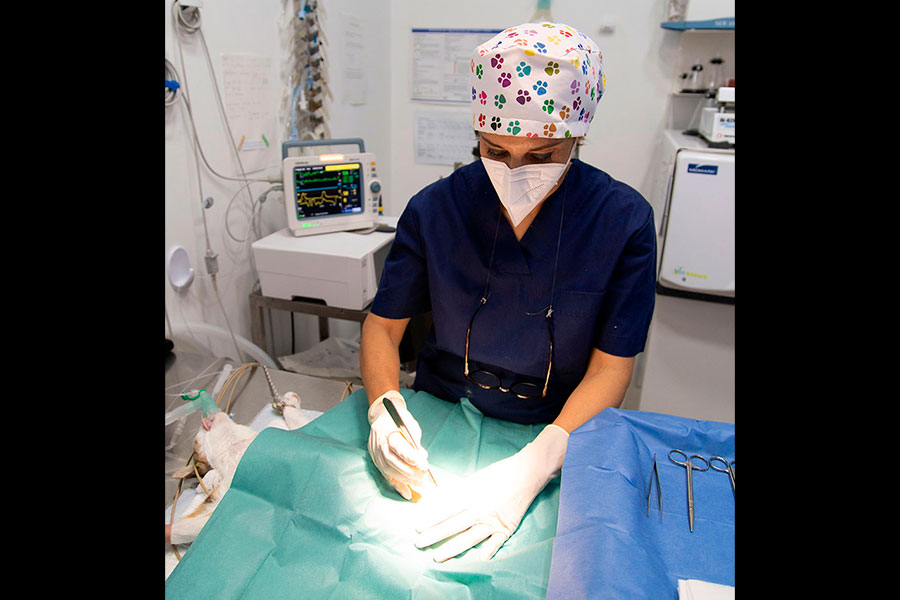

Cirugías

Nuestro quirófano está totalmente equipado con la última tecnología en aparatología, monitorización y equipos de anestesia.

Nuestra misión y objetivo es garantizar la total seguridad a nuestros pacientes durante cualquier tipo de intervención quirúrgica.

Tu mascota en las mejores manos

Mascotas felices, clientes satisfechos